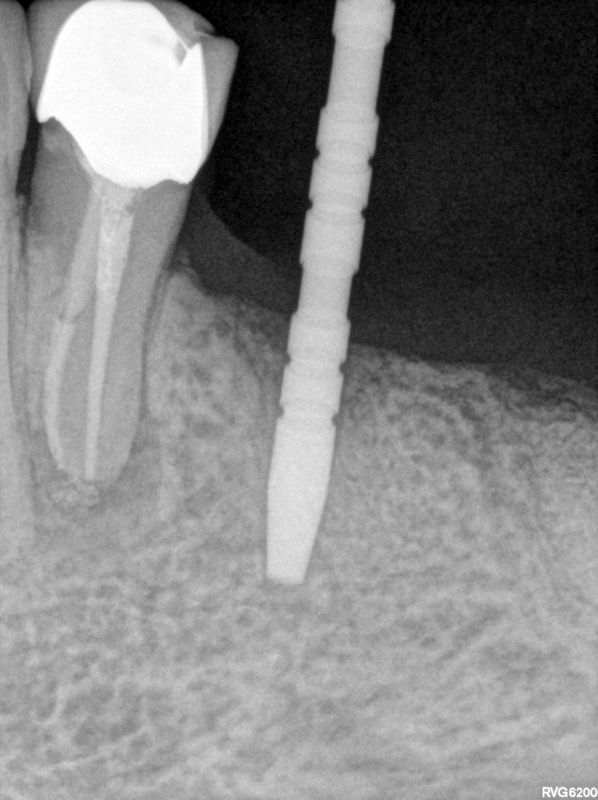

fredlibc | all galleries >> Galleries >> WYu implants 3536 > R3.jpg

R3.jpg